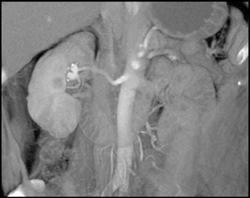

Renal Artery Aneurysm